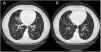

We report the case of a 34-year-old man, referred to the pulmonology department for multiple recurrent respiratory infections since childhood. Other issues include obesity, polydactyly, hypogonadism, mental retardation, and retinitis pigmentosa. He reported persistent productive cough. The study was completed with a computed tomography scan of the chest (Fig. 1A, B) that showed images of bilateral bronchiectasis and bronchiolectasis predominantly in the middle fields and lower lobes of both hemithoraces. Spirometry showed moderate airflow obstruction, a bronchodilator test was negative, and intermittent Streptococcus pneumoniae infection limited to exacerbations was detected. A sweat test and full laboratory tests were performed, including immunoglobulins, all of which were negative; however, in view of his morphological characteristics, the patient was referred to the genetics department, where he was finally diagnosed with Bardet–Biedl syndrome.

(A, B) Computed tomography images showing bilateral bronchiectasis and bronchiolectasis predominantly in the middle fields and lower lobes of both hemithoraces. Other findings included distal branched images and centriacinar nodules measuring around 1mm, associated with distal airway involvement.